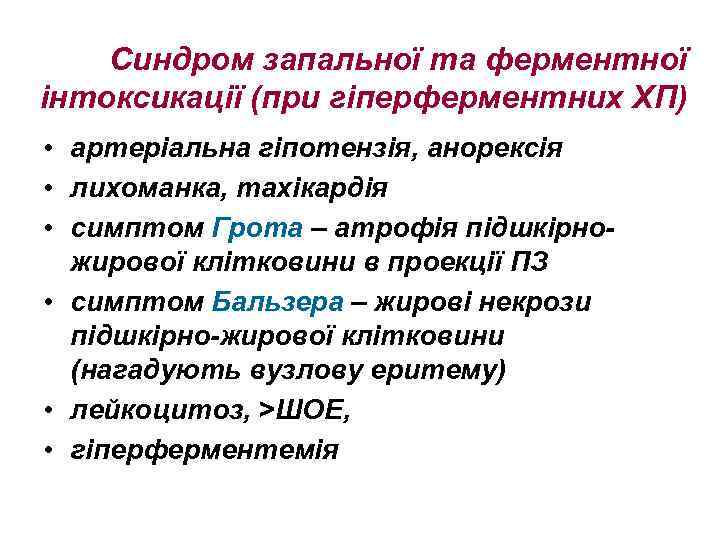

Синдром запальної та ферментної інтоксикації (при гіперферментних ХП) • артеріальна гіпотензія, анорексія • лихоманка, тахікардія • симптом Грота – атрофія підшкірножирової клітковини в проекції ПЗ • симптом Бальзера – жирові некрози підшкірно-жирової клітковини (нагадують вузлову еритему) • лейкоцитоз, >ШОЕ, • гіперферментемія

Синдром запальної та ферментної інтоксикації (при гіперферментних ХП) • артеріальна гіпотензія, анорексія • лихоманка, тахікардія • симптом Грота – атрофія підшкірножирової клітковини в проекції ПЗ • симптом Бальзера – жирові некрози підшкірно-жирової клітковини (нагадують вузлову еритему) • лейкоцитоз, >ШОЕ, • гіперферментемія